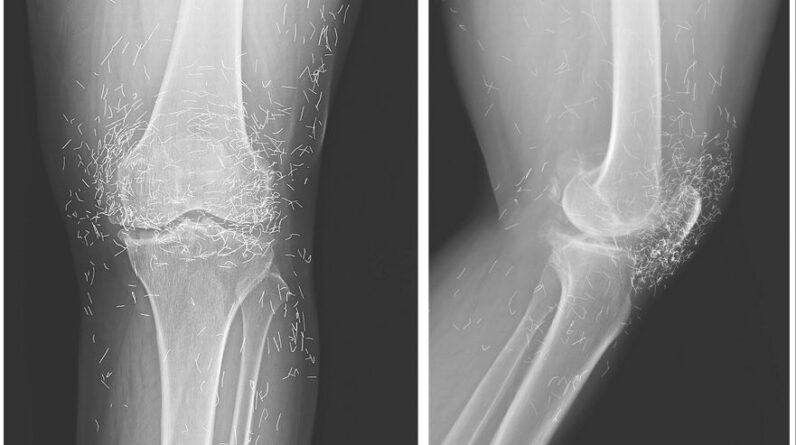

She later on went to the health center due to the fact that her knees were really aching. X-rays of her left knee exposed that the shinbone in the inner part of the joint had actually thickened and solidified. There were likewise bony developments, called stimulates, on the insides of the shinbone and thigh bone by the knee joint.

The physicians likewise saw numerous flecks on the X-ray around the knee joint, which ended up being small gold threads.

In their report of the knee case, the medical professionals kept in mind that gold threads placed throughout acupuncture can make it challenging to check out X-rays.